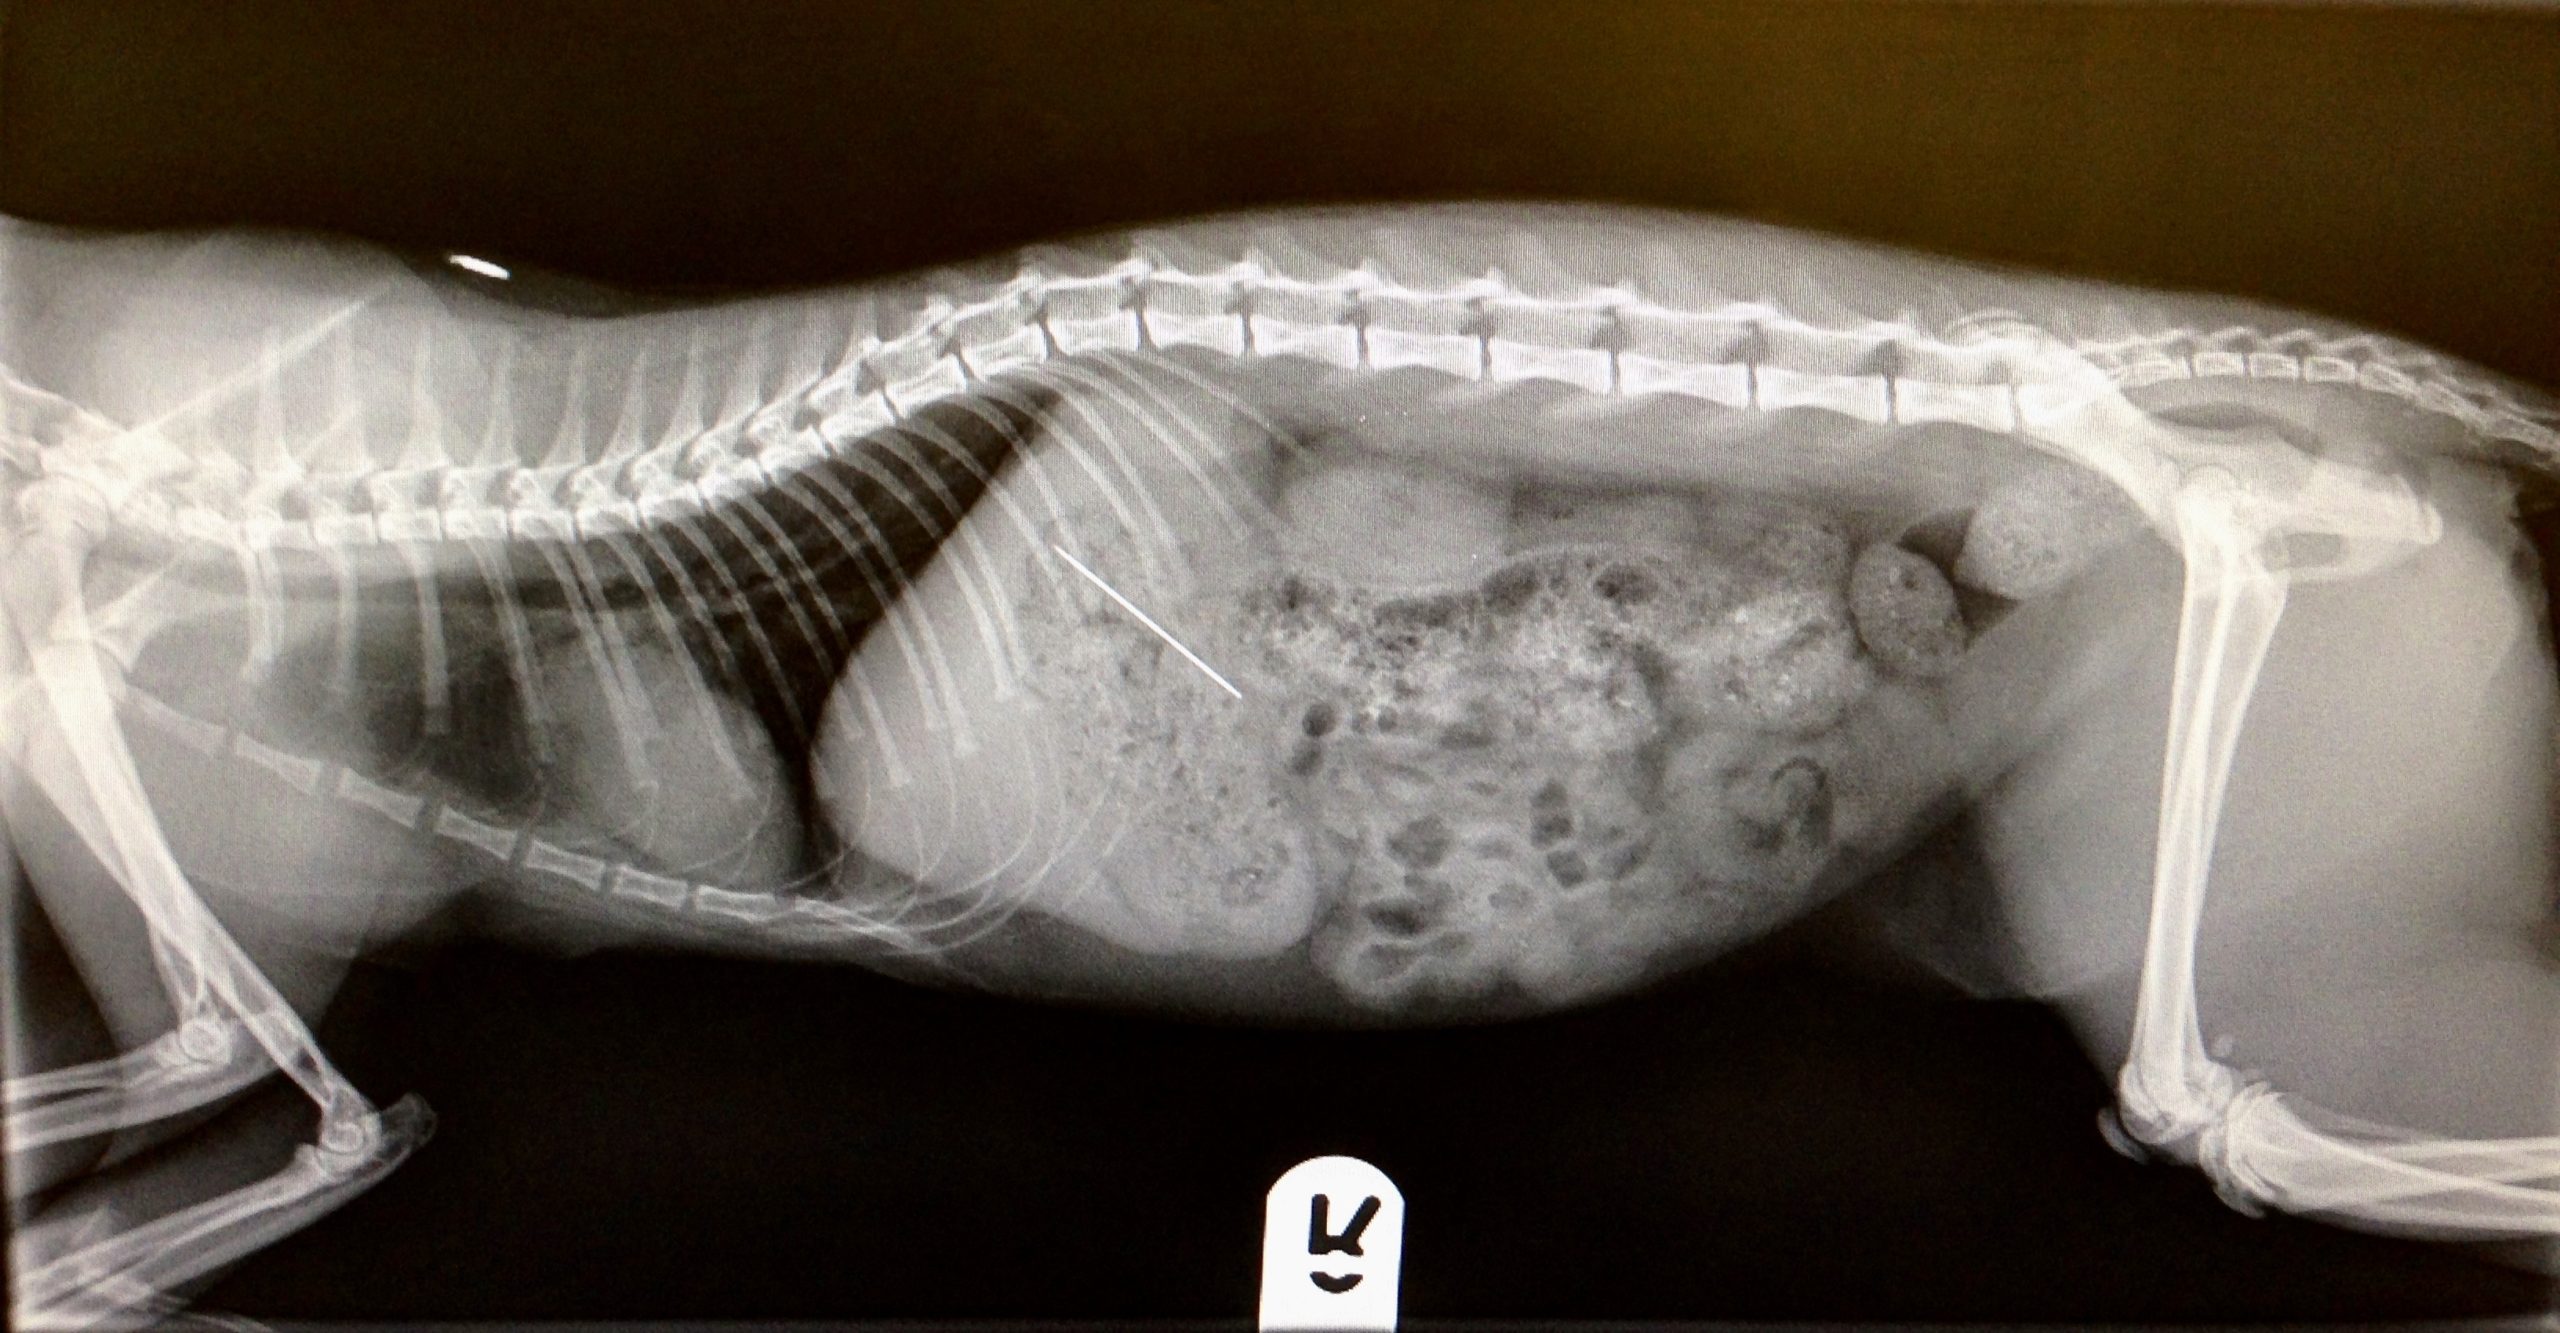

Imaging

We have digital radiography on site which means we can take an x-ray of your pet and have an exquisitely detailed image, on screen, in a few seconds. This means your pet is sedated or anaesthetised for a shorter period of time which helps reduce any risks. We have conventional x-ray as above, and also dental x-ray. The standard of care in veterinary dentistry has improved over the last decade, and good quality dental work does require support from dental x-rays, especially so for cats where they can have hidden dental lesions below the gumline.

Also in our imaging suite, is an outstanding ultrasound machine, the standard of which would meet that required for referral cardiology. The better the machine, the more accurate the images and report will be, which ultimately means more robust diagnoses and better outcomes for our animal patients. Investing in quality medical equipment and experienced, passionate staff to be the best for your beloved pets is the Whisker & Woof way.